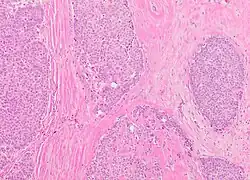

Histopathology of solid papillary carcinoma, H&E stain, showing large nests with solid sheets of tumor cells with (in this case variable amount of) fibrovascular cores.

Solid papillary carcinoma

Microscopic histopathological analyses of SPC lesions (refer to adjacent high-power photomicrograph) generally show tumors with multiple circumscribed nodules of expanded ducts filled with neoplastic epithelial cells which may appear spindle-shaped or plasma cell-like, have red to pink cytoplasm due to the uptake of eosin after staining with hematoxilin & eosin, and eccentrically-placed nuclei. Rarely, signet ring-shaped cells are present. The tumors may have cystic and hemorrhagic areas. Myoepithelial cells are found within and at the periphery of these tumors. The papillary architecture seen in the other SCB types is in general not apparent; rather, pseudo-rosettes (i.e. radial arrangements of neoplastic cells around small blood vessel) and nuclear palisading (i.e. parallel arrangements of the nuclei in rows of tumors that resembles picket fences) around stromal cores (i.e. supporting tissues) may be seen. SPC tumor tissues typically (>50% of cases) have areas of neuroendocrine differentiation. The presence of these areas strongly supports the diagnosis of SPC.[21] The signet ring-shaped cells in these tumors contain cytoplasmic mucin-containing vacuoles which push their cells' nuclei to one side.[10] Mucin may also occur outside of cells in these lesions. The presence of signet ring-shaped cells bearing mucin-containing vacuoles with or without extracellular mucin strongly supports the diagnosis of SPC. SPC is considered invasive when the tumor nests have a characteristic jigsaw growth pattern with ragged and irregular margins with the loss of myoepithelial cells at the site(s) of invasion.[21] Rarely, invasive SPC occurs with nearby invasive carcinoma of NST, lobular carcinoma, cribriform carcinoma, or tubular carcinoma breast tumors.[3]